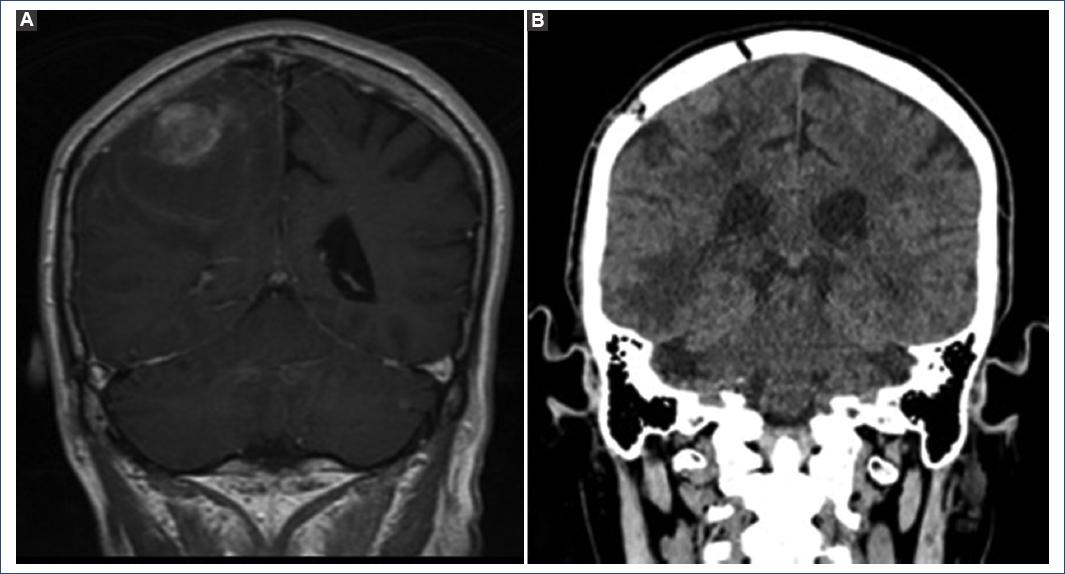

A stereotactic-guided resection of the right frontoparietal lesion was done. The pathology report documented melanoma metastasis with immunohistochemical markers HMB45-red, S 100 MELAN a, and Ki67 50%, with no BRAF mutation identified. Two months after the resection, he received a dose of immunotherapy with nivolumab without any adverse effects (Fig. 2).

Figure 2 A: pre-operative magnetic resonance imaging in coronal section T1 sequence, right parietal lesion of heterogeneous intensity with ring contrast enhancement. B: simple computed axial tomography in coronal section, right parietal craniotomy, and total resection.